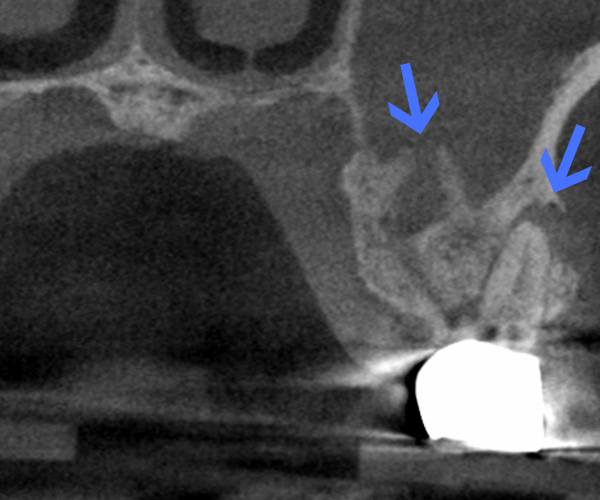

Before

歯性上顎洞炎(副鼻腔炎)

根尖病巣により洞底膜がラッパ状に開いている。

After

6ヶ月後のCT

洞底膜はきれいに再生され病巣は消失しております。